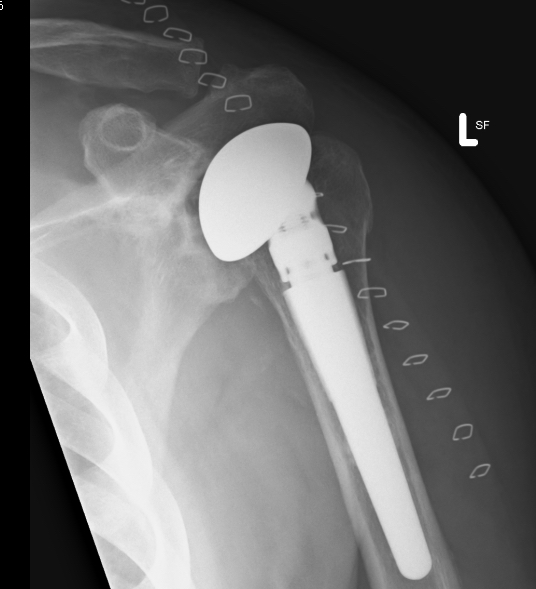

Anatomical TSA

Reverse TSA

aTSA v revTSA for OA

Parada et al. J Should Elbow Surg 2021

- 2224 aTSA revision rate 5.6%

- 4158 revTSA revision rate 2.5%